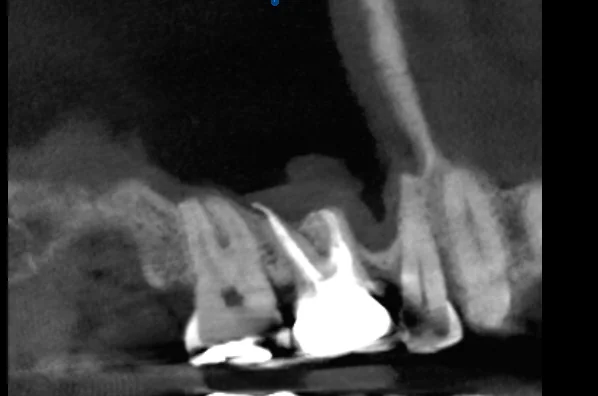

CBCT Assessment

A CBCT scan was obtained to definitively rule out dental pathology. The three-dimensional imaging confirmed:

• No periapical radiolucencies on any teeth in the region

• No evidence of fractures, cracks, or resorptive lesions

• Intact lamina dura and normal periodontal ligament space

• No pathology that would warrant endodontic intervention

• CBCT imaging: Three-dimensional views eliminated the ambiguity inherent in 2D radiographs

• CBCT resolves ambiguity: When 2D radiographs are inconclusive, three-dimensional imaging provides definitive answers. The cost of a CBCT scan is trivial compared to the cost of treating the wrong tooth.